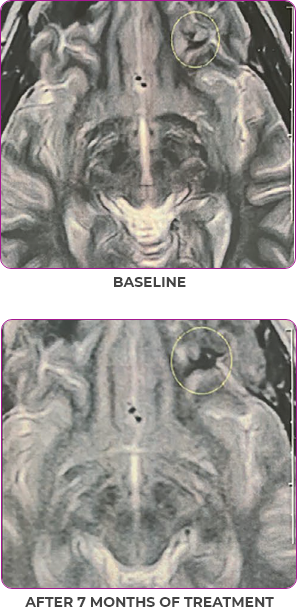

MRIa imagery of the brain. Green circles indicate baseline brain metastases.1

Response in primary and metastatic lesions1

SCAN 2: BRAIN

aMRI, magnetic resonance imaging.

MRIa imagery of the brain. Green voxels indicate decreased burden of metastatic disease; further quantified by accompanying measurement in green.1

SCAN 3: BRAIN

Pre- and post-treatment imaging, by Rosen EY et al, is licensed under Creative Commons License CC BY 4.0.